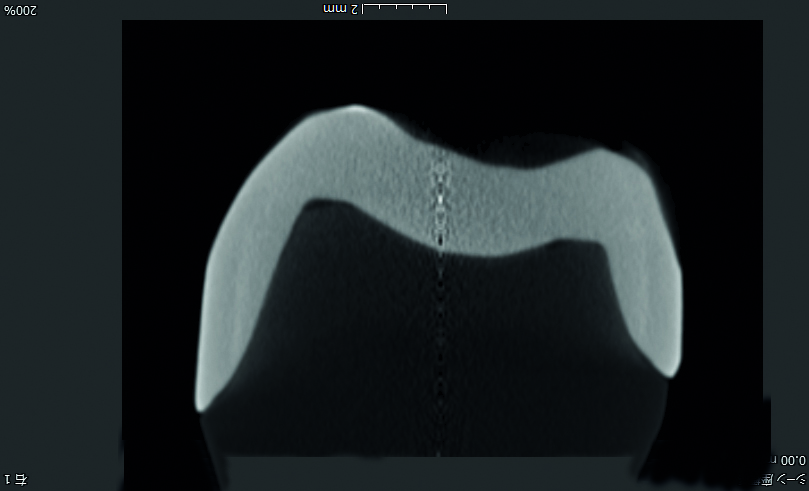

Limites plus précises

Étant entièrement cristallisé avant fraisage, Initial™ LiSi Block peut être fraisé directement avec des limites cervicales lisses et précises. Autrement, il peut être cuit après coloration et conserver une grande précision des limites cervicales.

Comparaison de Initial™ LiSi Block avec IPS e.max CAD en termes de limites cervicales :

GC LiSi block vs e.max cadInitial™ LiSi Block

GC LiSi block vs e.max cadIPS e.max CAD